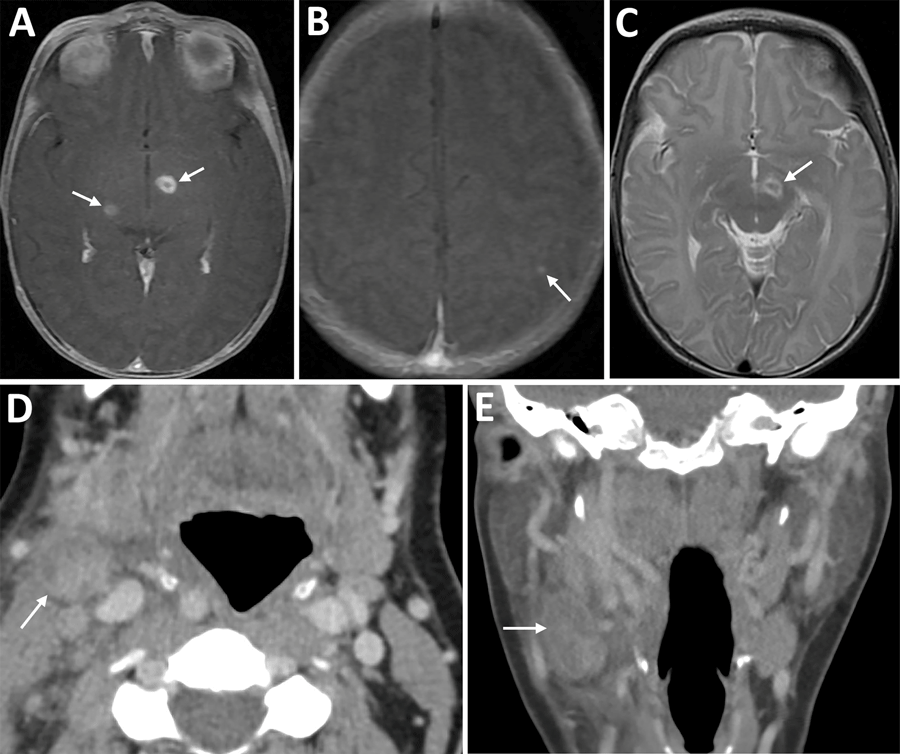

Figure 1. Imaging from infant and mother in case of congenital tularemia with neuroinvasive disease, Utah, USA. A, B) Axial T1 post-contrast images showing the infant’s initial magnetic resonance imaging findings of rim enhancing lesions near the left subthalamic nucleus and right inferior thalamus (arrows, panel A), as well as a punctate enhancing lesion in the left parietal lobe (arrow, panel B). C) Axial T2 image demonstrating T2 hyperintense edema along the margins of the largest lesion near the left subthalamic nucleus (arrow). D, E) Axial (D) and coronal (E) images from the mother’s computed tomography scan with intravenous contrast showing an enlarged, heterogeneous right cervical chain lymph node with inflammatory stranding in the adjacent soft tissues (arrows).